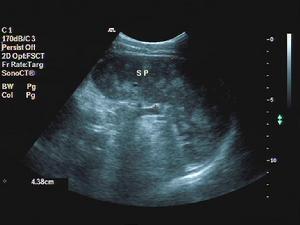

遊走脾的診斷一般並不困難,必要時可作以下輔助檢查:①B型超音波,左膈下正常脾臟消失,而在腹塊處呈現脾臟反射。②核素掃描,如51Cr標記檢查,可發現腹塊有同位素積聚,並見明顯的腹塊輪廓。③選擇性腹腔動脈造影可見到腫塊的血管供應來自脾動脈。④CT檢查。

檢查:行B超、CT檢查或核素掃描等影像學檢查可明確診斷。